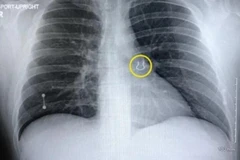

30/09/2022 16:12 Một người đàn ông 35 tuổi sống tại Mỹ đã bị sốc nặng khi biết rằng chiếc khuyên mũi mà anh làm thất lạc cách đây 5 năm thực ra đang nằm yên ở một bên phổi.